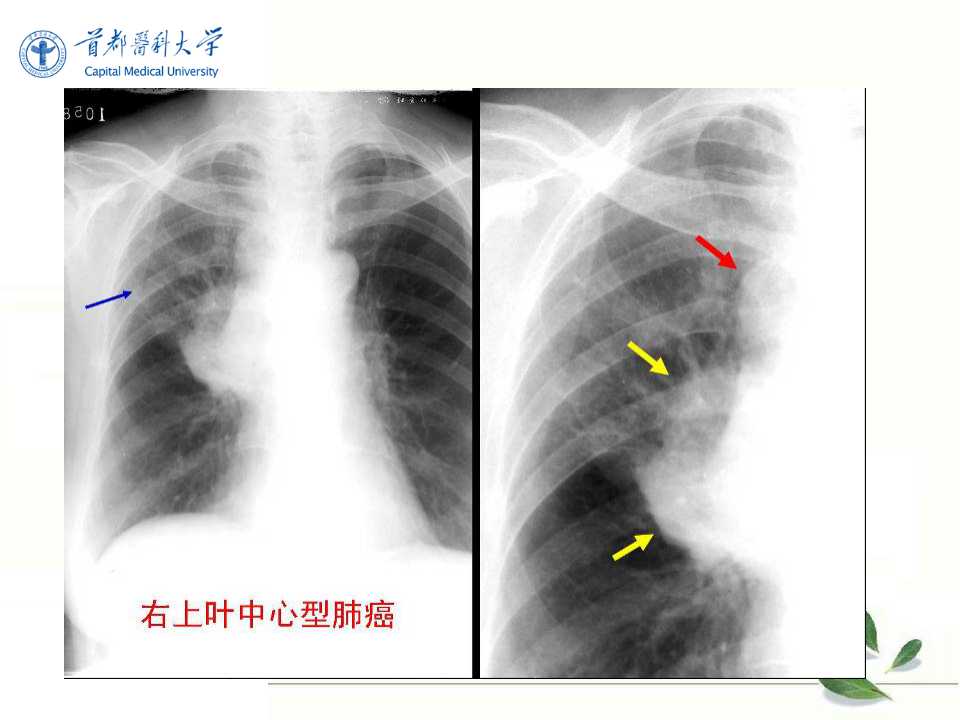

肺癌的影像学检查